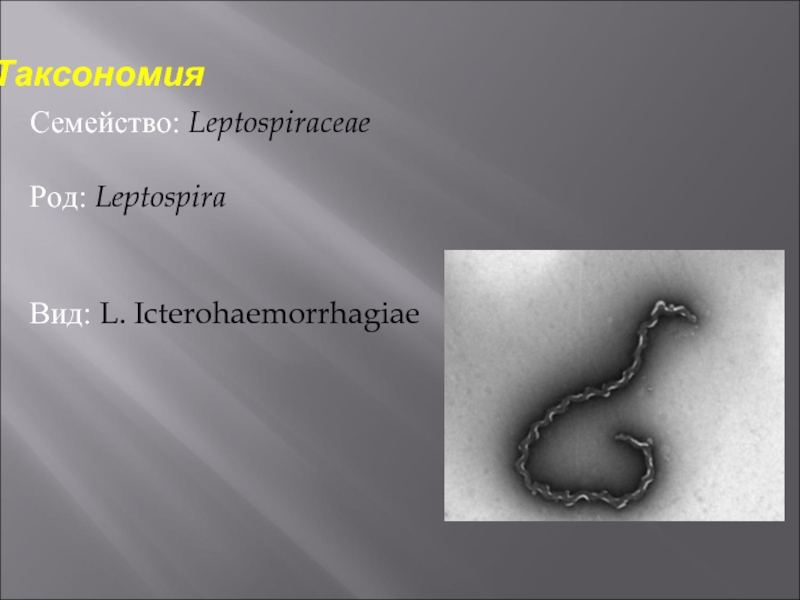

Лептоспиры: фотографии удивительных микроорганизмов